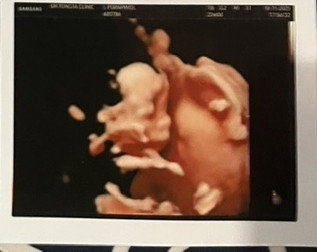

ถึงเจ้าตัวเล็กของแม่... รู้ไหมว่าทุกครั้งที่หนูดิ้นทักทาย แม่สัมผัสได้ถึงปาฏิหาริย์ที่กำลังเติบโตอยู่ในตัวแม่เลยนะ ตอนนี้แม่กับพ่อตื่นเต้นกันสุดๆ เตรียมของใช้รอต้อนรับหนูแทบไม่หวาดไม่ไหว แม่เฝ้านับวันรอที่จะได้เห็นหน้าสบตา และได้อุ้มหนูไว้ในอ้อมกอดจริงๆ สักที โลกข้างนอกนี้กว้างใหญ่และสวยงามมากนะลูก แม่ไม่ได้หวังให้หนูต้องเก่งกว่าใคร แค่อยากให้หนูโตมาเป็นเด็กที่มีความสุข มีรอยยิ้มที่สดใส และรู้ไว้เสมอว่าไม่ว่าจะเกิดอะไรขึ้น หนูจะมีแม่กับพ่อที่รักและคอยซัพพอร์ตหนูอยู่ตรงนี้ตลอดไป ขอบคุณนะลูกที่เลือกมาเป็นลูกของแม่ อดทนเติบโตไปด้วยกันอีกนิดนะ แล้วเจอกันมิถุนายนนี้ครับเจ้าตัวแสบ! รักหนูที่สุดในโลก จาก... แม่เอง

Đọc thêmถึงลูกรักของแม่ ตอนนี้ลูกอยู่ในท้องแม่ได้5เดือนแล้ว แม่เฝ้าทะนุถนอมตั้งแต่เจอ2ขีดเลยนะ ตั้งแต่ท้องพ่อกับแม่ทะเลาะกันน้อยลงเราทั้ง2จะตั้งใจทำเพื่อหนูนะลูก ตอนแรกแม่อยากได้ผู้หญิงแต่หมอบอกว่าแม่ได้ลูกชาย ไม่เป็นไรนะผู้ชายแม่ก็รัก แม่ฝันว่าลูกเกิดมาเป็นผู้ชายแล้วบอกแม่ว่าหนูจะเป็นกระเทยให้แม่เอง หนูคงน้อยใจแม่ ไม่เป็นไรนะลูกผู้หญิงหรือผู้ชายแม่ก็รักเพราะหนูคือดวงใจของแม่ แม่ขออวยพรให้หนูสมบูรณ์แข็งแรงและรอวันเจอหน้าหนูทุกวันขอให้หนูคลอดออกมาอย่างปลอดภัยและแข็งแรงนะลูก แม่จะรอโอบกอดลูกนะ(แม่พิมพ์เสร็จแล้วอ่านให้ลูกฟังด้วยลูกตอดแม่ด้วย รักลูกนะครับ)

แม่ท้อง